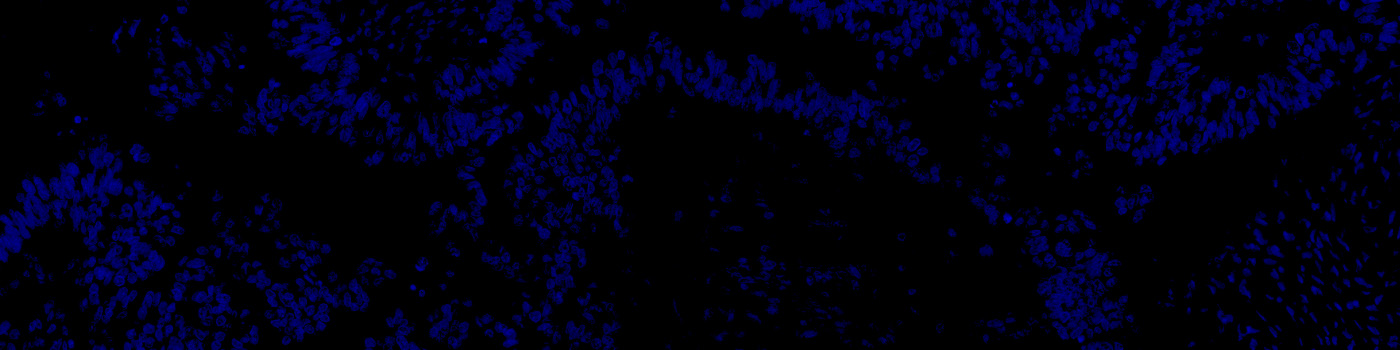

Tissue stained with DAPI

Identification and segmentation of individual nuclei is of interest in many applications. Nuclei can be difficult to detect accurately and precisely across different images using traditional image analysis with feature engineering. This APP utilizes artificial intelligence (AI) for automatic nuclear segmentation in fluorescence images stained with a family of blue dyes for DNA identification. It consists of a pre-trained deep neural network and the APP is ready for use without additional training.

The APP was trained using 41,000 annotated nuclei from DAPI stained tissue. The architectural structure of the network is a U-Net which is popular for medical image segmentation. The neural network uses a cascade of layers of nonlinear processing units for feature extraction and transformation, with each successive layer using the output from the previous layers as input. U-Net uses an encoder-decoder structure with a contracting path and an expansive path. For more information of the network architecture, see [1].

Tissue must be labeled with a blue fluorescent dye for DNA staining such as DAPI, Hoechst or Iridium such that all nuclei are labeled.